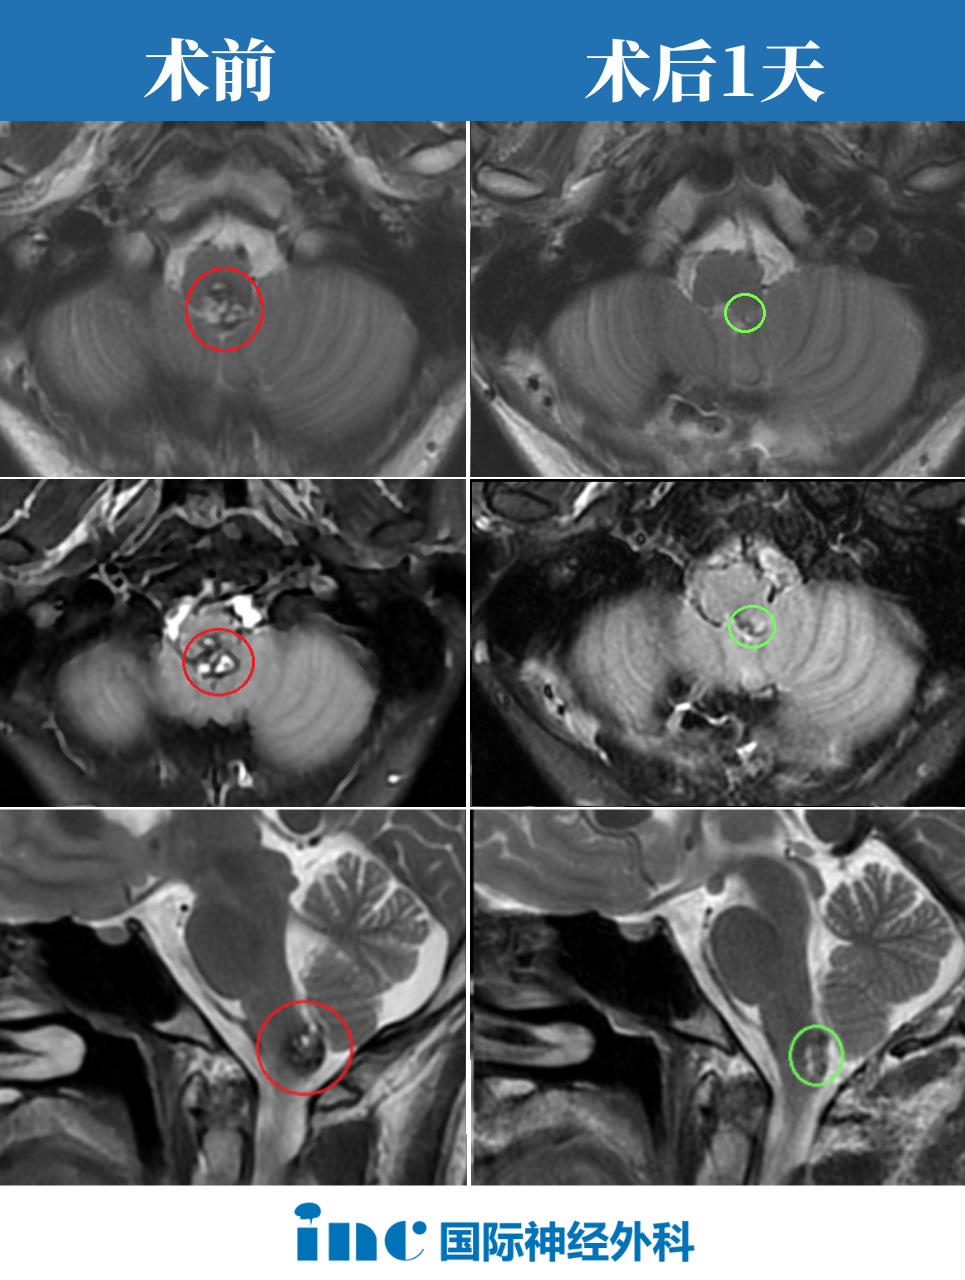

手术完成后,包括影像结果,我也请当地神经外科医生查看。他惊叹:“效果非常神奇,手术如此彻底,如此成功!关键恢复极快,一天即出ICU,且神志清晰。”儿子甚至主动打电话确认,认为难以置信。

我表示他在ICU期间就与我视频联系。第二天基本可下地活动,48小时后完成MRI检查,独立走入检查室。至今,患者的反应、神志、吞咽功能等基本状态良好,仅手部麻木,我认为后期定能恢复。一切顺利,毫无问题!目前我几乎无担忧。